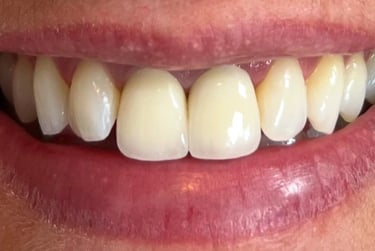

Aspecto Clínico Final - Fotografias originais — nenhuma contém retoques — A cor dos dentes é escolhida de acordo com o gosto e a preferência estética de cada paciente.

Coroas em Dissilicato de Lítio

Todos os caso a seguir estão associadas a clareamento dentário